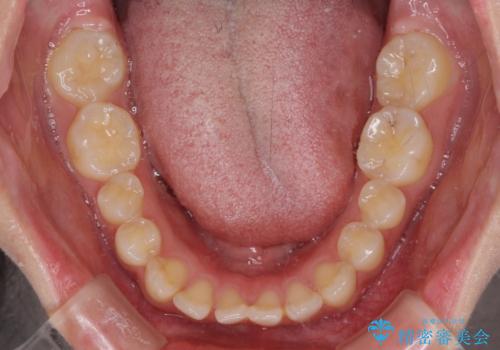

上下前歯同士の距離が離れているため、上顎左右第一小臼歯2本を抜歯することで前突を改善することとしました。

しかしながら、左右ともに側切歯が矮小歯であるため、矯正治療で矮小歯前後にスペースを作り、矯正治療後にオールセラミッククラウンにて補綴治療を行うこととしました。

治療途中で地元へ転居され、飛行機での通院となったため、治療期間が長くなりましたが、自然で整った口元に仕上げることができました。